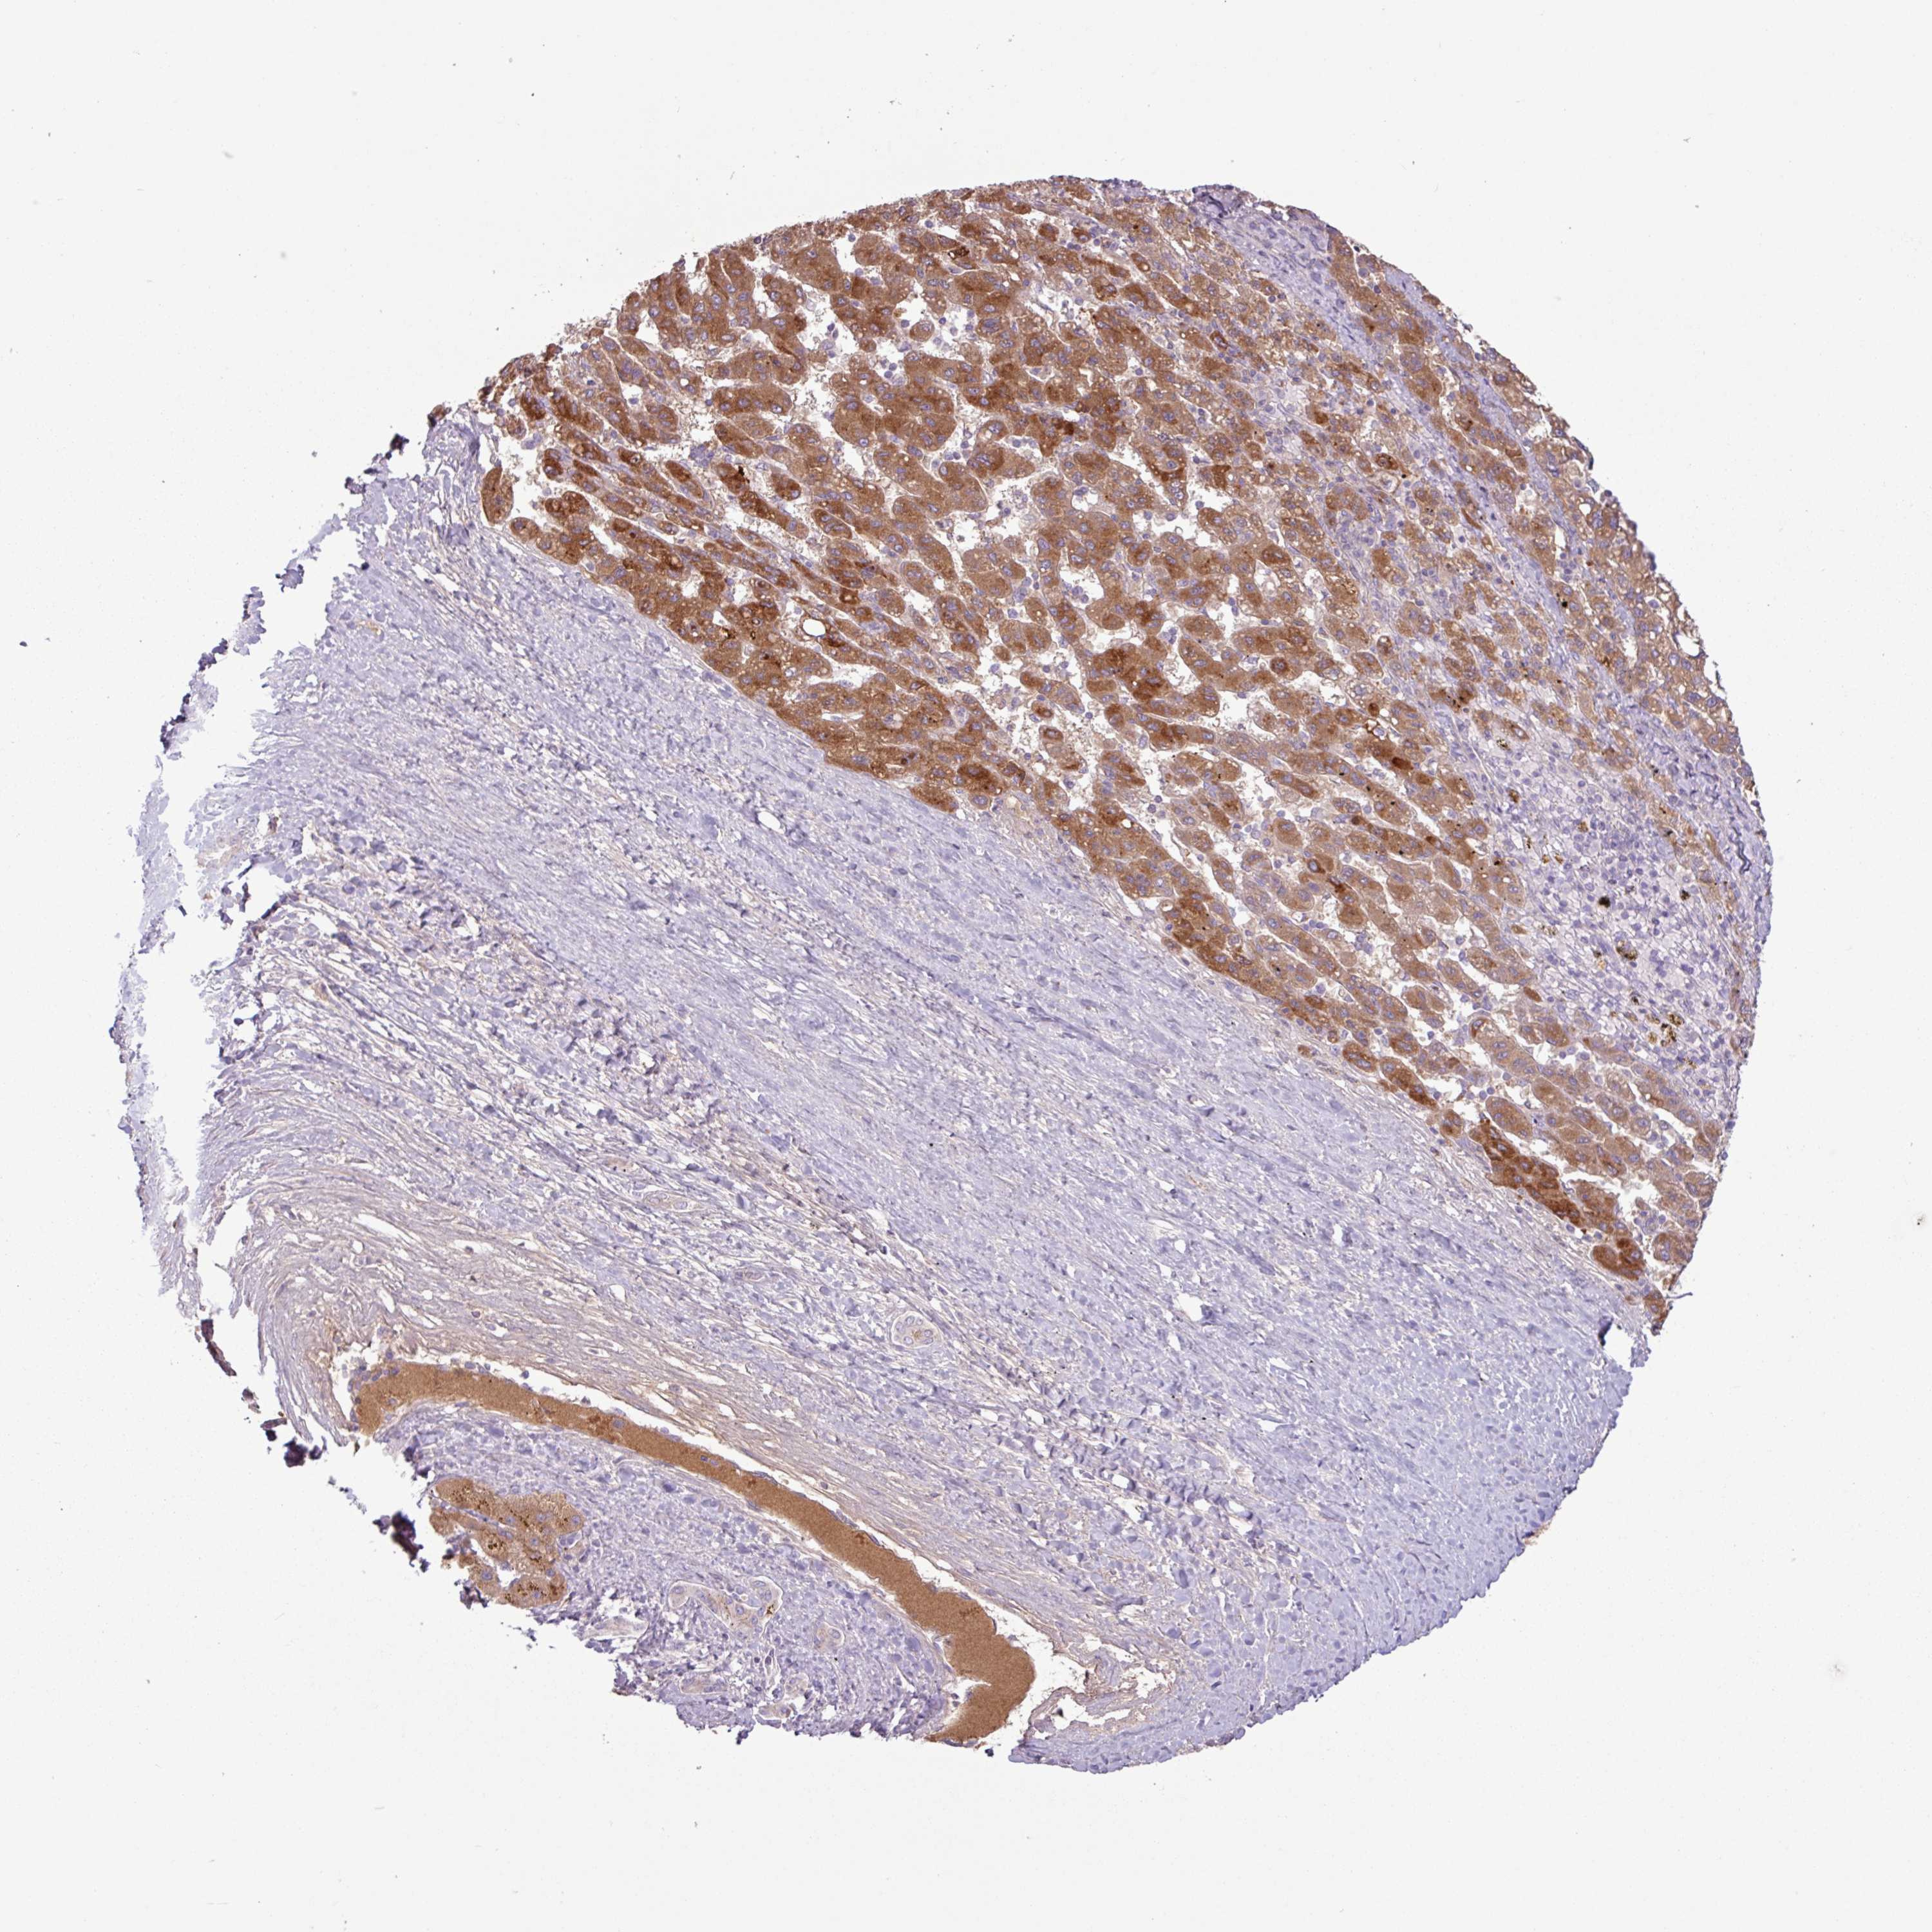

LIVER CANCER - Protein expressioni

A mouse-over function shows sample information and annotation data. Click on an image to view it in a full screen mode. Samples can be filtered based on level of antibody staining by selecting one or several of the following categories: high, medium, low and not detected. The assay and annotation is described here.

Note that samples used for immunohistochemistry by the Human Protein Atlas do not correspond to samples in the TCGA dataset.

Antibody stainingi

Antibody staining in the annotated cell types in the current human tissue is reported as not detected, low, medium, or high, based on conventional immunohistochemistry profiling in selected tissues. This score is based on the combination of the staining intensity and fraction of stained cells.

Each image is clickable and will lead to virtual microscopy that enables deeper exploration of all samples and also displays staining intensity scores, fraction scores and subcellular localization as well as patient and tissue information for each sample.

HPA046356

HPA048287

HPA050103

CAB009811

CAB032603

Staining

High

Medium

Low

Not detected

Intensity

Strong

Moderate

Weak

Negative

Quantity

>75%

75%-25%

<25%

None

Location

Nuclear

Cytoplasmic/membranous

Cytoplasmic/membranous,nuclear

Cholangiocarcinoma

Carcinoma, Hepatocellular, NOS